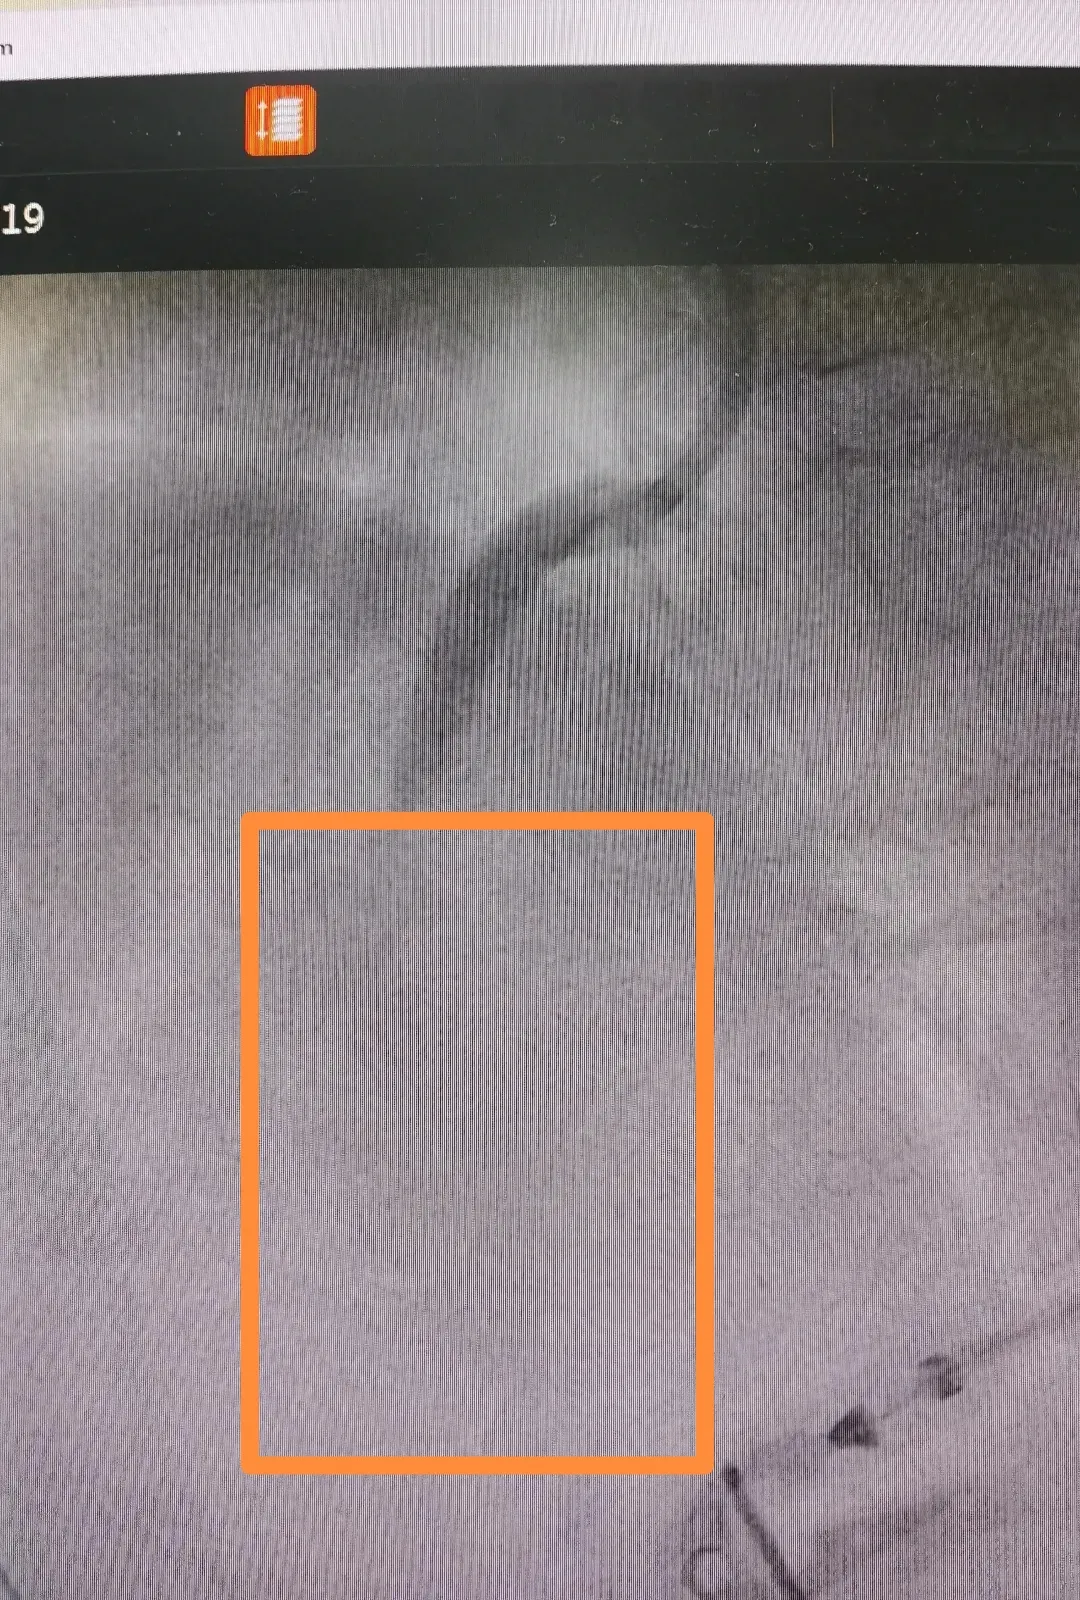

介入团队紧密配合,缜密操作,造影发现患者左冠中度狭窄,右冠近段闭塞,手术团队以精准的操作快速开通右冠闭塞,随着血液重新灌注,患者症状和体征逐渐好转,三度恢复,心率开始恢复,血压维持稳定。

造影显示右冠近段闭塞